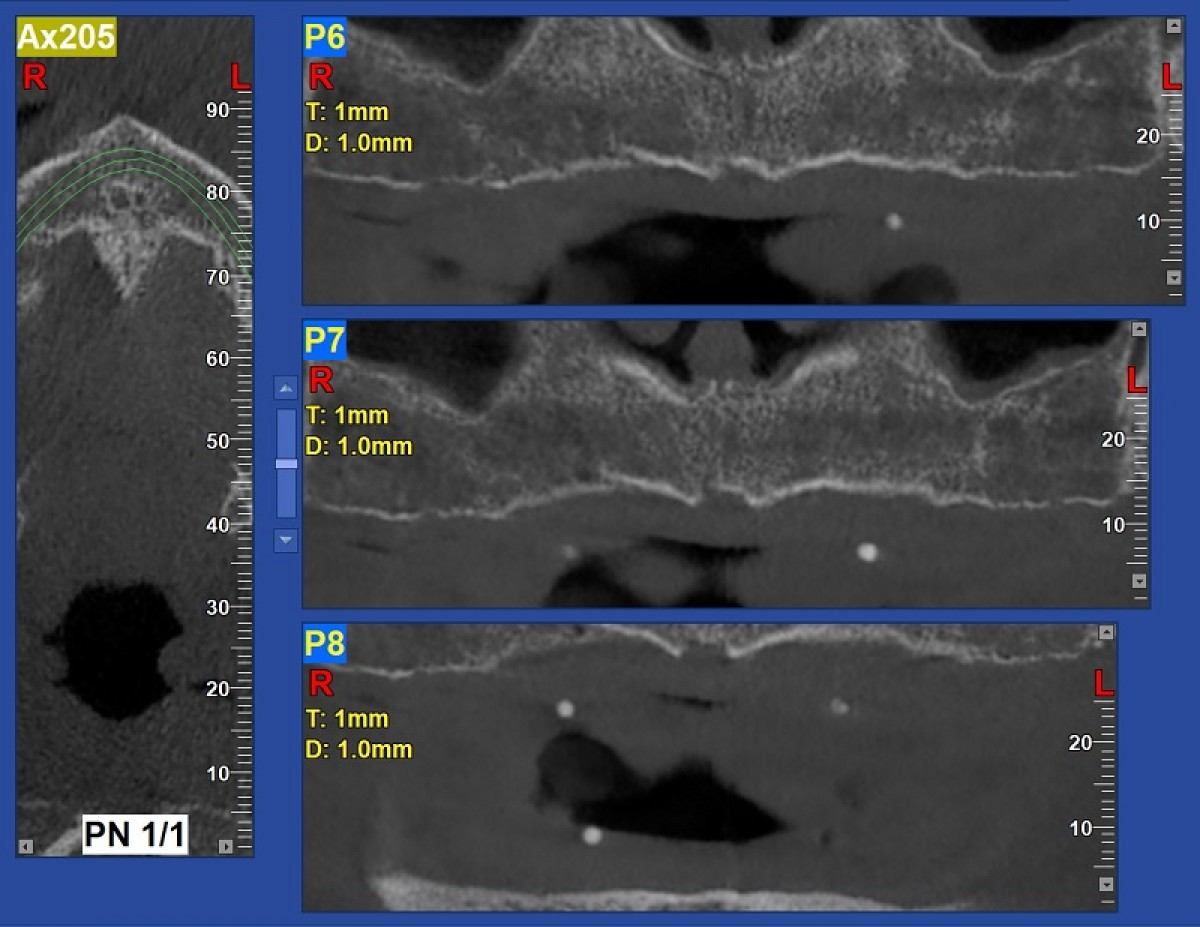

The cephalometric VTO allowed us to identify the exact movements the incisors need to make in the sagittal and vertical planes. To complete the three-dimensional treatment planning, the virtual set-up was used. The dental arches were further scanned using the Trios (3Shape) scanner (fig. 6).

The intraoral scan file was then uploaded to the Insigna (Ormco) web application where the arches were segmented (i.e. the teeth were separated from each other) and an initial virtual set-up was performed by Insigna technicians. Subsequently - again on the Insigna web application - we perfected and completed the virtual set-up. The settings for the position and the angle of the upper and lower incisors were based on the cephalometric VTO values (fig. 7).